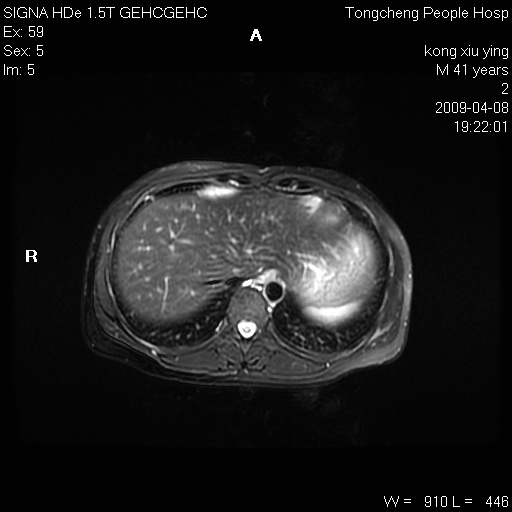

标题: CL1008:【经典】胆囊石榴籽样结石。 [打印本页]

标题: CL1008:【经典】胆囊石榴籽样结石。

女,41岁。健康体检——彩超提示:胆囊显示不清。平素健康,无不适感。

腹部mr扫描及mrcp,图像如下: